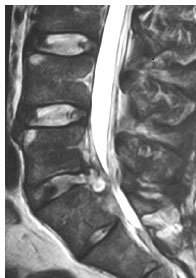

Maschio di 45 anni. Avanza anche questo lentamente. Si tiene una mano sulla coscia quasi spingendola per avanzare con minor fatica. E’ sempre utile osservare come i pazienti entrano nel box del pronto soccorso. Si siede con fatica. E ti racconta. Da 4 giorni comparsa di lombalgia con irradiazione lungo la superficie laterale dell’arto inferiore sinistro fino al piede. Ha assunto paracetamolo 1 g cp per 3 volte al giorno per 3 giorni e “magnesio naturale” consigliato dal farmacista. Non fatemi commentare. Comunque sia, il beneficio è stato scarsissimo. Riferisce inoltre che tali sintomi li aveva già avuti 2 anni prima, protratti, per cui aveva eseguito RM che evidenziava ernia discale a livello di L5. Non la porta in visione causa perdita durante il trasloco. Nient’altro in anamnesi. Lo visiti.

Dolore alla palpazione della regione lombare. Lasegue positivo a sin. Lieve riduzione della forza alla dorsiflessione del piede sin e all’estensione delle dita. Sensibilità ridotta a livello dell’avampiede sin. Riflessi osteotendinei normoeccitabili. Restante obiettività completamente negativa.

Lo dimetti con diagnosi di “RADICULOPATIA ACUTA LOMBOSACRALE SINISTRA” (evitate il termine “sciatica” per favore) e gli consigli terapia con: naprossene 250 mg x 2 volte al giorno per almeno 10 giorni, oxicodone/naloxone 10/5 x 2 volte al die per 10 giorni e quindi rivalutazione dal curante.

Bene. Anamnesi, clinica, obiettività non fanno stare tranquilli. Chiederei una RM ma nel nostro ospedale c’è solo un giorno/settimana e fuori sede. Chiedo dunque una TC rachide toraco-lombo-sacrale che conferma il sospetto: trasferisco quindi il paziente in ospedale di riferimento (dotato di servizio di chirurgia spinale e infettivologia) con diagnosi di :

“ASCESSO SPINALE EPIDURALE A LIVELLO L3-S1”